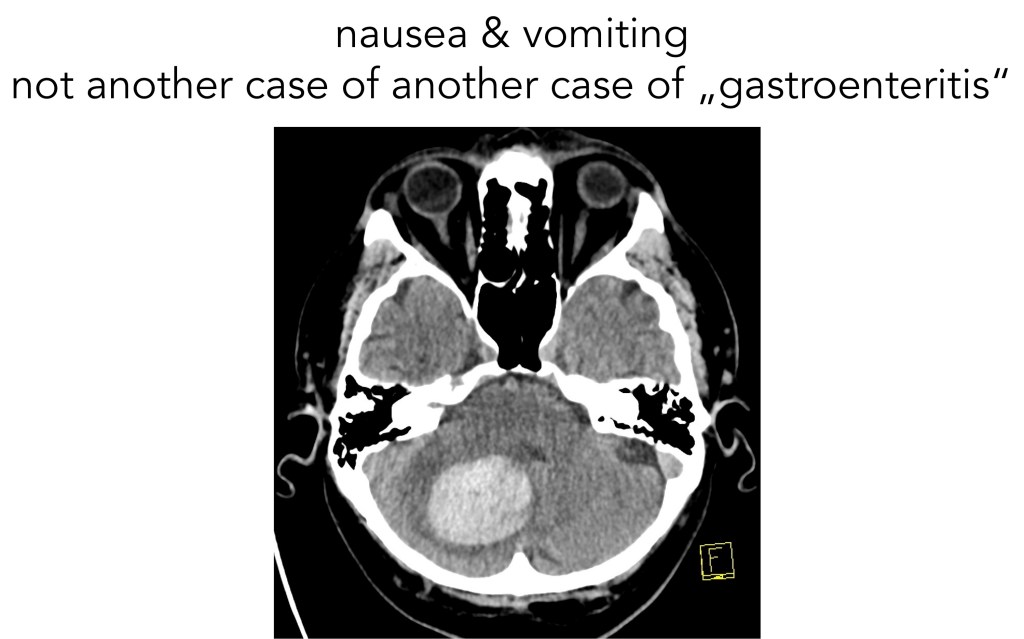

NO gastroenteritis